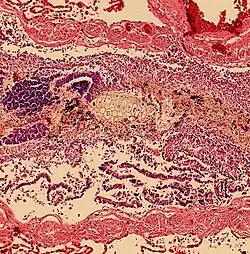

Aspiration pneumonia

Aspiration pneumonia is when bacteria is carried into the respiratory tract via aspiration and subsequently causes an infection of the lung. Any substance or object that is aspirated into the airway has the potential of carrying infectious agents with it into the respiratory tract. It primarily affects older adults and can be especially severe in patients with learning disabilities, or disorders of abnormal swallowing.[14]

Aspiration pneumonitis

Aspiration pneumonitis (Mendelson's syndrome) is chemical injury of lung tissue secondary to aspiration of regurgitated gastric acid.[15] The syndrome was first described among pregnant patients[16] after the administration of anesthesia, though it can occur in any scenario where gastric contents are aspirated.[17]